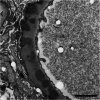

Case presentation: The patient was a 43-year-old Japanese man who had shown a high zinc sulfate value in turbidity test, polyclonal hypergammaglobulinemia, anemia, and proteinuria. A physical examination revealed diffuse lymphadenopathy, an enlarged spleen and papulae of the body trunk. A skin biopsy of a papule on the patient's back showed plasma cells in the perivascular area and he was diagnosed with multicentric Castleman's disease, plasma cell variant. Kidney biopsy showed the appearance of bubbling in the glomerular basement membranes in Periodic acid methenamine silver stain and electron microscopy revealed electron dense deposits within and outside the glomerular basement membranes. Since immunofluorescence study showed predominant granular deposition of IgG1 and IgG2, he was diagnosed with secondary membranous nephropathy associated with Castleman's disease. He was initially treated with prednisolone alone, however his biochemical abnormalities did not improve. After intravenous tocilizumab (700 mg every 2 weeks) was started, his C-reactive protein elevation, anemia, and polyclonal gammopathy improved. Furthermore, his urinary protein level declined from 1.58 g/gCr to 0.13 g/gCr. The prednisolone dose was gradually tapered, then discontinued. He has been stable without a recurrence of proteinuria for more than 6 months.